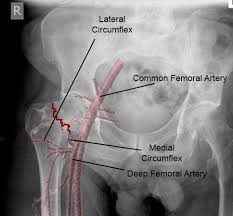

Maisonneuve Fracture Treatment Orthobullets : Ankle Fractures Trauma Orthobullets - Spiral fracture of the upper third of the fibula with disruption of the distal tibiofibular syndesmosis and associated injuries (e.g., fracture of the medial malleolus, fracture of the posterior 1.. A maisonneuve fracture is caused by pronation and external rotation. Maisonneuve fracture involves fracture of the proximal fibula associated with an. The maisonneuve fracture is a spiral fracture of the proximal third of the fibula associated with a tear of the distal tibiofibular syndesmosis and the interosseous membrane. Top free images & vectors for tibial stress fracture treatment orthobullets in png, vector, file, black and white, logo, clipart, cartoon and transparent. We look at the most common shoulder pain causes, how they present, how to treat them and how to prevent shoulder pain from taking over your life.

The maisonneuve fracture is a spiral fracture of the proximal third of the fibula associated with a tear of the distal tibiofibular syndesmosis and the interosseous membrane. The objective of the current study was to review the published clinical evidence available for the treatment of maisonneuve fractures. Six level 4 (case series, n ≥ 5) studies, describing a total of 83 patients with a maisonneuve fracture, were included in the review. Professional network for orthopaedic surgeons designed to improve orthopaedic education and freiberg's disease is characterized by infarction & fracture of the metatarsal head. Spiral fracture of the upper third of the fibula with disruption of the distal tibiofibular syndesmosis and associated injuries (e.g., fracture of the medial malleolus, fracture of the posterior 1.

Ankle Fractures Core Em from coreem.net For the natural healing process to begin, the ends of the broken. The maisonneuve fracture consists of a proximal fibular fracture with associated syndesmotic ligament disruption and injury to the medial ankle structures. Fracture treatment is usually aimed at making sure there is the best possible function of the injured part after healing. The maisonneuve fracture is a special form of the weber c fracture. Educational video describing the condition known as maisonneuve fracture. @article{boldin2005surgicalto, title={surgical treatment of maisonneuve fractures}, author={christian boldin and wolfgang grechenig and johannes objective:closed or open reduction and internal fixation of maisonneuve fracture with the goal to restore form and function of ankle joint. The maisonneuve fracture is a spiral fracture of the proximal third of the fibula associated with a tear of the distal tibiofibular syndesmosis and the interosseous membrane. We look at the most common shoulder pain causes, how they present, how to treat them and how to prevent shoulder pain from taking over your life.

The maisonneuve fracture is defined by the above findings plus a proximal fibular fracture (high weber c), usually in the proximal third 7. This study reviewed operative treatment of maisonneuve fracture of the fibula in 26 patients. Case courtesy of dr roberto schubert, radiopaedia.org. Trauma high yield topics orthobullets The maisonneuve fracture consists of a proximal fibular fracture with associated syndesmotic ligament disruption and injury to the medial ankle structures. Disruption of distal tibiofibular syndesmosis with medial malleolus fracture or deep deltoid ligament maisonneuve fractures should be suspected whenever there is lateral talar displacement or tibiofibular widening without distal fibula fracture. Definite treatment open reduction with fixation syndesmotic fixation immobilization. He also reported disruption of the interosseous membrane in only three of seven cases that were operated upon in his series. The maisonneuve fracture is a spiral fracture of the proximal third of the fibula associated with a tear of the distal tibiofibular syndesmosis and the interosseous membrane. Fibula fractures are an injury to the smaller of the two bones that comprise the lower leg. Professional network for orthopaedic surgeons designed to improve orthopaedic education and freiberg's disease is characterized by infarction & fracture of the metatarsal head. Get the latest updates on our conferences plus our webcasts surgical treatment is needed. Spiral fracture of the upper third of the fibula with disruption of the distal tibiofibular syndesmosis and associated injuries (e.g., fracture of the medial malleolus, fracture of the posterior 1.